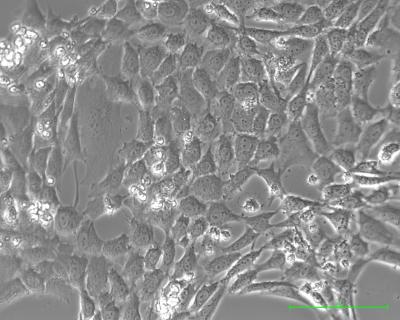

This shows pancreatic cancer cells growing in laboratory dishes.

(Photo Credit: James Eshleman, Johns Hopkins University School of Medicine)